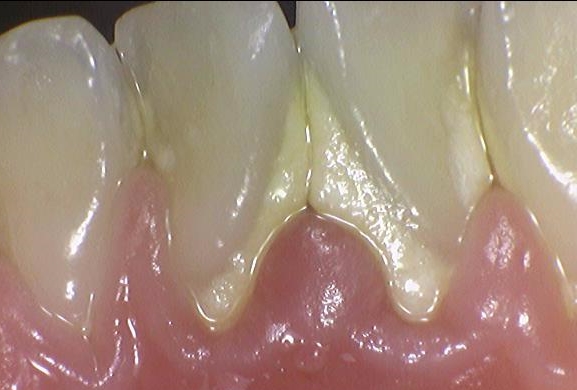

<스케일링>이란

스케일링이란 치아 표면에 붙어있는 치석을 제거하는 시술입니다.

잇몸 위에 치아에 붙어있는 보이는 치석을 제거하는 것이지요.

잇몸주변과 치아에 노란 치석이 붙어있는 것을 볼 수 있습니다.